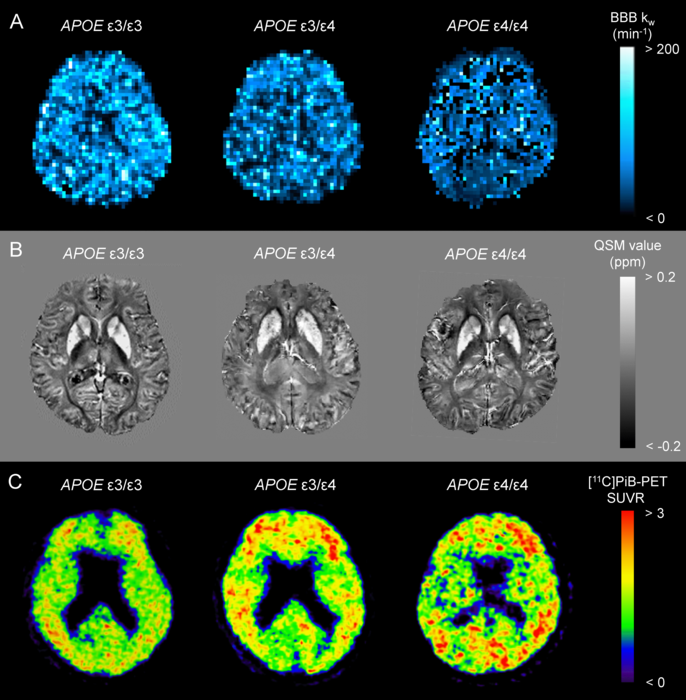

image: BBB kw map (A), QSM (B), and [11C]PiB-PET SUVR (C) from an APOE ɛ4 noncarrier (ε3/ε3), a heterozygote (ε3/ε4), and a homozygote (ε4/ε4) are displayed. view more

First, we presented the clinical characteristics and neuropsychological scores for APOE ɛ4 noncarrier, heterozygous, and homozygous groups from the early stages of the Alzheimer's continuum cohort. Second, we compared AD-related imaging biomarkers, including the BBB kw map, quantitative susceptibility mapping (QSM), [11C]Pittsburgh compound B-positron emission tomography (PiB-PET), and cortical thickness. Finally, we assessed the correlation of kw values with neuroimaging metrics of AD pathology and neuropsychological scores. We concluded that APOE ɛ4 dose would be associated with poor brain-waste clearance through the BBB, causing brain iron and Aβ accumulation.